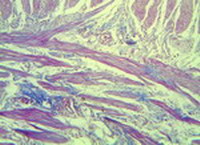

Աղիների լորձաթաղանթի տարբեր հատվածներում բակտերիոցիդ հյութի քանակությունը տարբեր է, որի մասին էն վկայում Պաննետի բջիջների ուսումնասիրության տվյալները. կան էպիթելային խորշիկներ, որտեղ այս բջիջների քանակությունը բավարար է, ինչը վկայում էֆուքսինոֆիլ հյութի բարձր պարունակության մասին: Սրա հարևանությամբ նկատվում են նաև Պաննետի բջիջներ չպարունակող խորշեր, ինչը մատնանշում է լորձաթաղանթի տեղային մանրեասպան հնարավորությունների անկարողությունը (նկ. 2):

Նկար 2. Լիբերկյունի կրիպտաները (դրանցից երկուսում նշմարվում են ֆուքսիֆիլգրանուլաներ, իսկ մյուսներում՝ ոչ): Պիկրո-Մալորի 200 | Նկար 3. Ենթալորձային շերտի լայնացած երակիկներ, որոնք պարունակում ենդրական հիալինային թրոմբեր: PAS-ռեակցիան լրացուցիչ Մայերիհեմատոքսիլինով ներկված: PAS |